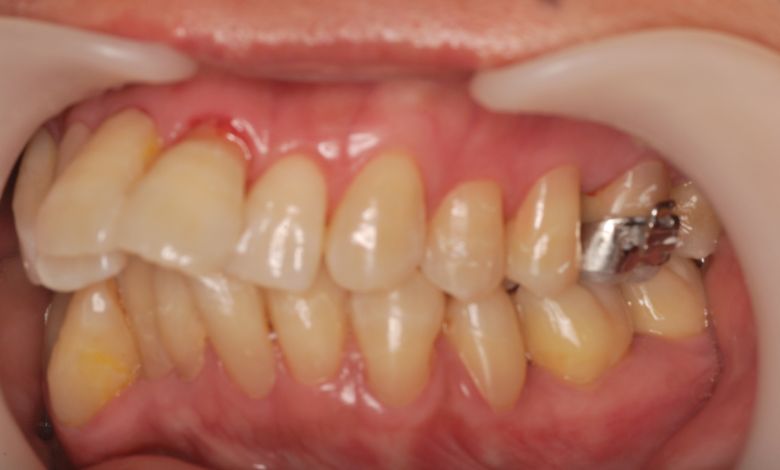

他院にて上下左右4本の抜歯を前提とした矯正治療を提案されていました。上顎・下顎ともに歯列弓が狭く、

V字型の弓状を呈していたため、叢生(歯の重なり)が強く、噛み合わせにも不調和が見られる状態でした。

上顎歯列はV字型に近く、全体的にアーチが狭窄している状態

上下の咬合関係も不正で、機能的にも審美的にも問題のある状態でした

歯列弓はV字型に狭く、左右の犬歯が唇側に大きく転位している状態

上下の前歯に強い重なりが見られます。特に上顎犬歯と下顎前歯のズレが顕著で、自然な咬合が形成されていない